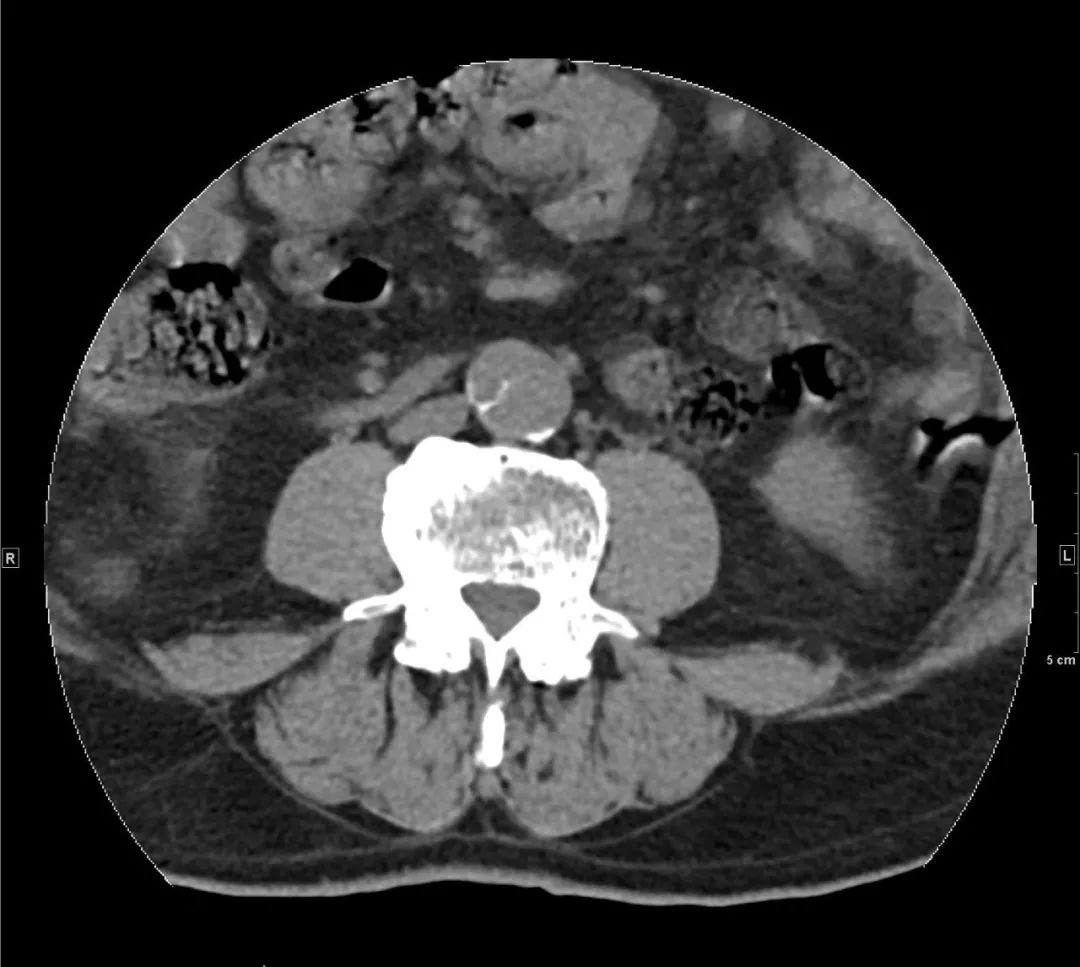

患者的腰椎间盘突出不是严重,之所以将患者家属喊来询问病史,是因为看到了腹主动脉血管壁钙化,确切的说是“不一样”血管壁钙化,腹主动脉(双肾下极水平以下)内分隔影伴钙化(如下图):

正常情况下,老年人血管壁有钙化是再正常不过,但钙化即使再严重,也是呈环形贴着血管壁,上面这样钙化很怪异,分隔伴细条状钙化。如果没有任何症状,可能是正常的;但当有症状时,而且腰痛用正常的腰椎间盘突出难以解释时,不能除外一种相对少见但非常危险的情况——“主动脉夹层”。

腹主动脉CTA腹腔干水平(骨窗) 左侧髂总动脉(骨窗)